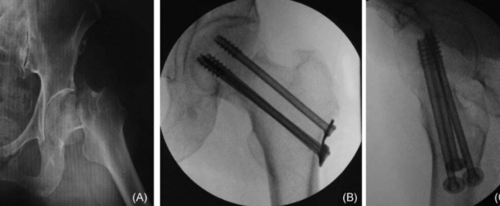

2、外固定器置入 :第一阶段是在两侧无名骨(受伤侧和未受伤侧)置入固定针。每个半骨盆采用双正交固定:额状面的髋臼上针和矢状面的 LC2 通道针。(图1a - 1b)此技术可增强头侧 / 尾侧复位控制并提高旋转稳定性。固定针设置如下:在标准前后位(AP)视图下,将额状面的髋臼上针置于髋臼眉弓上方,直达无名骨内板且避免损伤关节。对于 LC2 针,可用泪滴视图或 "Teepee" 视图(出口闭孔位)观察通道,但由于器械操作干扰,不一定需获取该视图。因针长及透视下对准通道轴有难度,故采用两个正交视图。髂骨视图用于确定髂前下棘(AIIS)的进针点,并引导头尾轨迹,目标是坐骨大切迹头侧。入口闭孔视图则确保针不置于盆内或盆外。

然后围绕患者组装固定架。图 1 展示了最全面的设置版本,依损伤情况也可选用更轻便版本。用横杆连接系统左右部分以增强稳定性,将骨盆未受伤侧 “锁定” 到相邻支架部分,以便更有效地操纵受伤侧。需识别关键放射学标志,入口位视图中包括耻骨联合前部和后部、骶髂关节前部(一侧坐骨支撑内板和另一侧骶骨翼)、骶椎前壁;出口位视图中包含耻骨联合(耻骨上支)、坐骨大切迹及其与骶骨形成的曲线、骶髂关节头侧部分和髂嵴。除标准入口位和出口位视图外,入口闭孔视图(“沿骶髂关节视图”)能清晰显示骶髂关节和髂结节外板,利于更精确控制髂骶骨(IS)或经骶骨(TS)螺钉的放置和长度。(图2)

共纳入 15 例患者,其中男 10 名,女 5 名,平均年龄 35 岁,平均 BMI 为 30。骨折类型包括侧方挤压型(LC)3 型骨折 5 例,前后挤压型(APC)3 型骨折 4 例,LC 2 型骨折 2 例,垂直剪切损伤 4 例。平均手术时间为 130 分钟,术后影像显示平均最大移位为 5.4 毫米,平均不对称性为 3.7 毫米(表1)。总体而言,大多数病例患者实现优秀或良好复位。